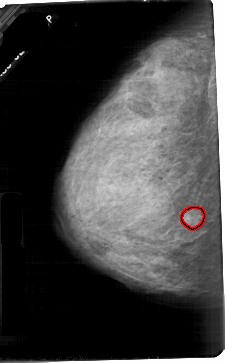

A_1678_1.LEFT_CC

LEFT_CC LINES 5431 PIXELS_PER_LINE 3361 BITS_PER_PIXEL 12 RESOLUTION 43.5 OVERLAY

FILE: A_1678_1.LEFT_CC.OVERLAY

TOTAL_ABNORMALITIES 1

ABNORMALITY 1

LESION_TYPE MASS SHAPE ROUND MARGINS ILL_DEFINED

ASSESSMENT 4

SUBTLETY 3

PATHOLOGY MALIGNANT

TOTAL_OUTLINES 1

BOUNDARY